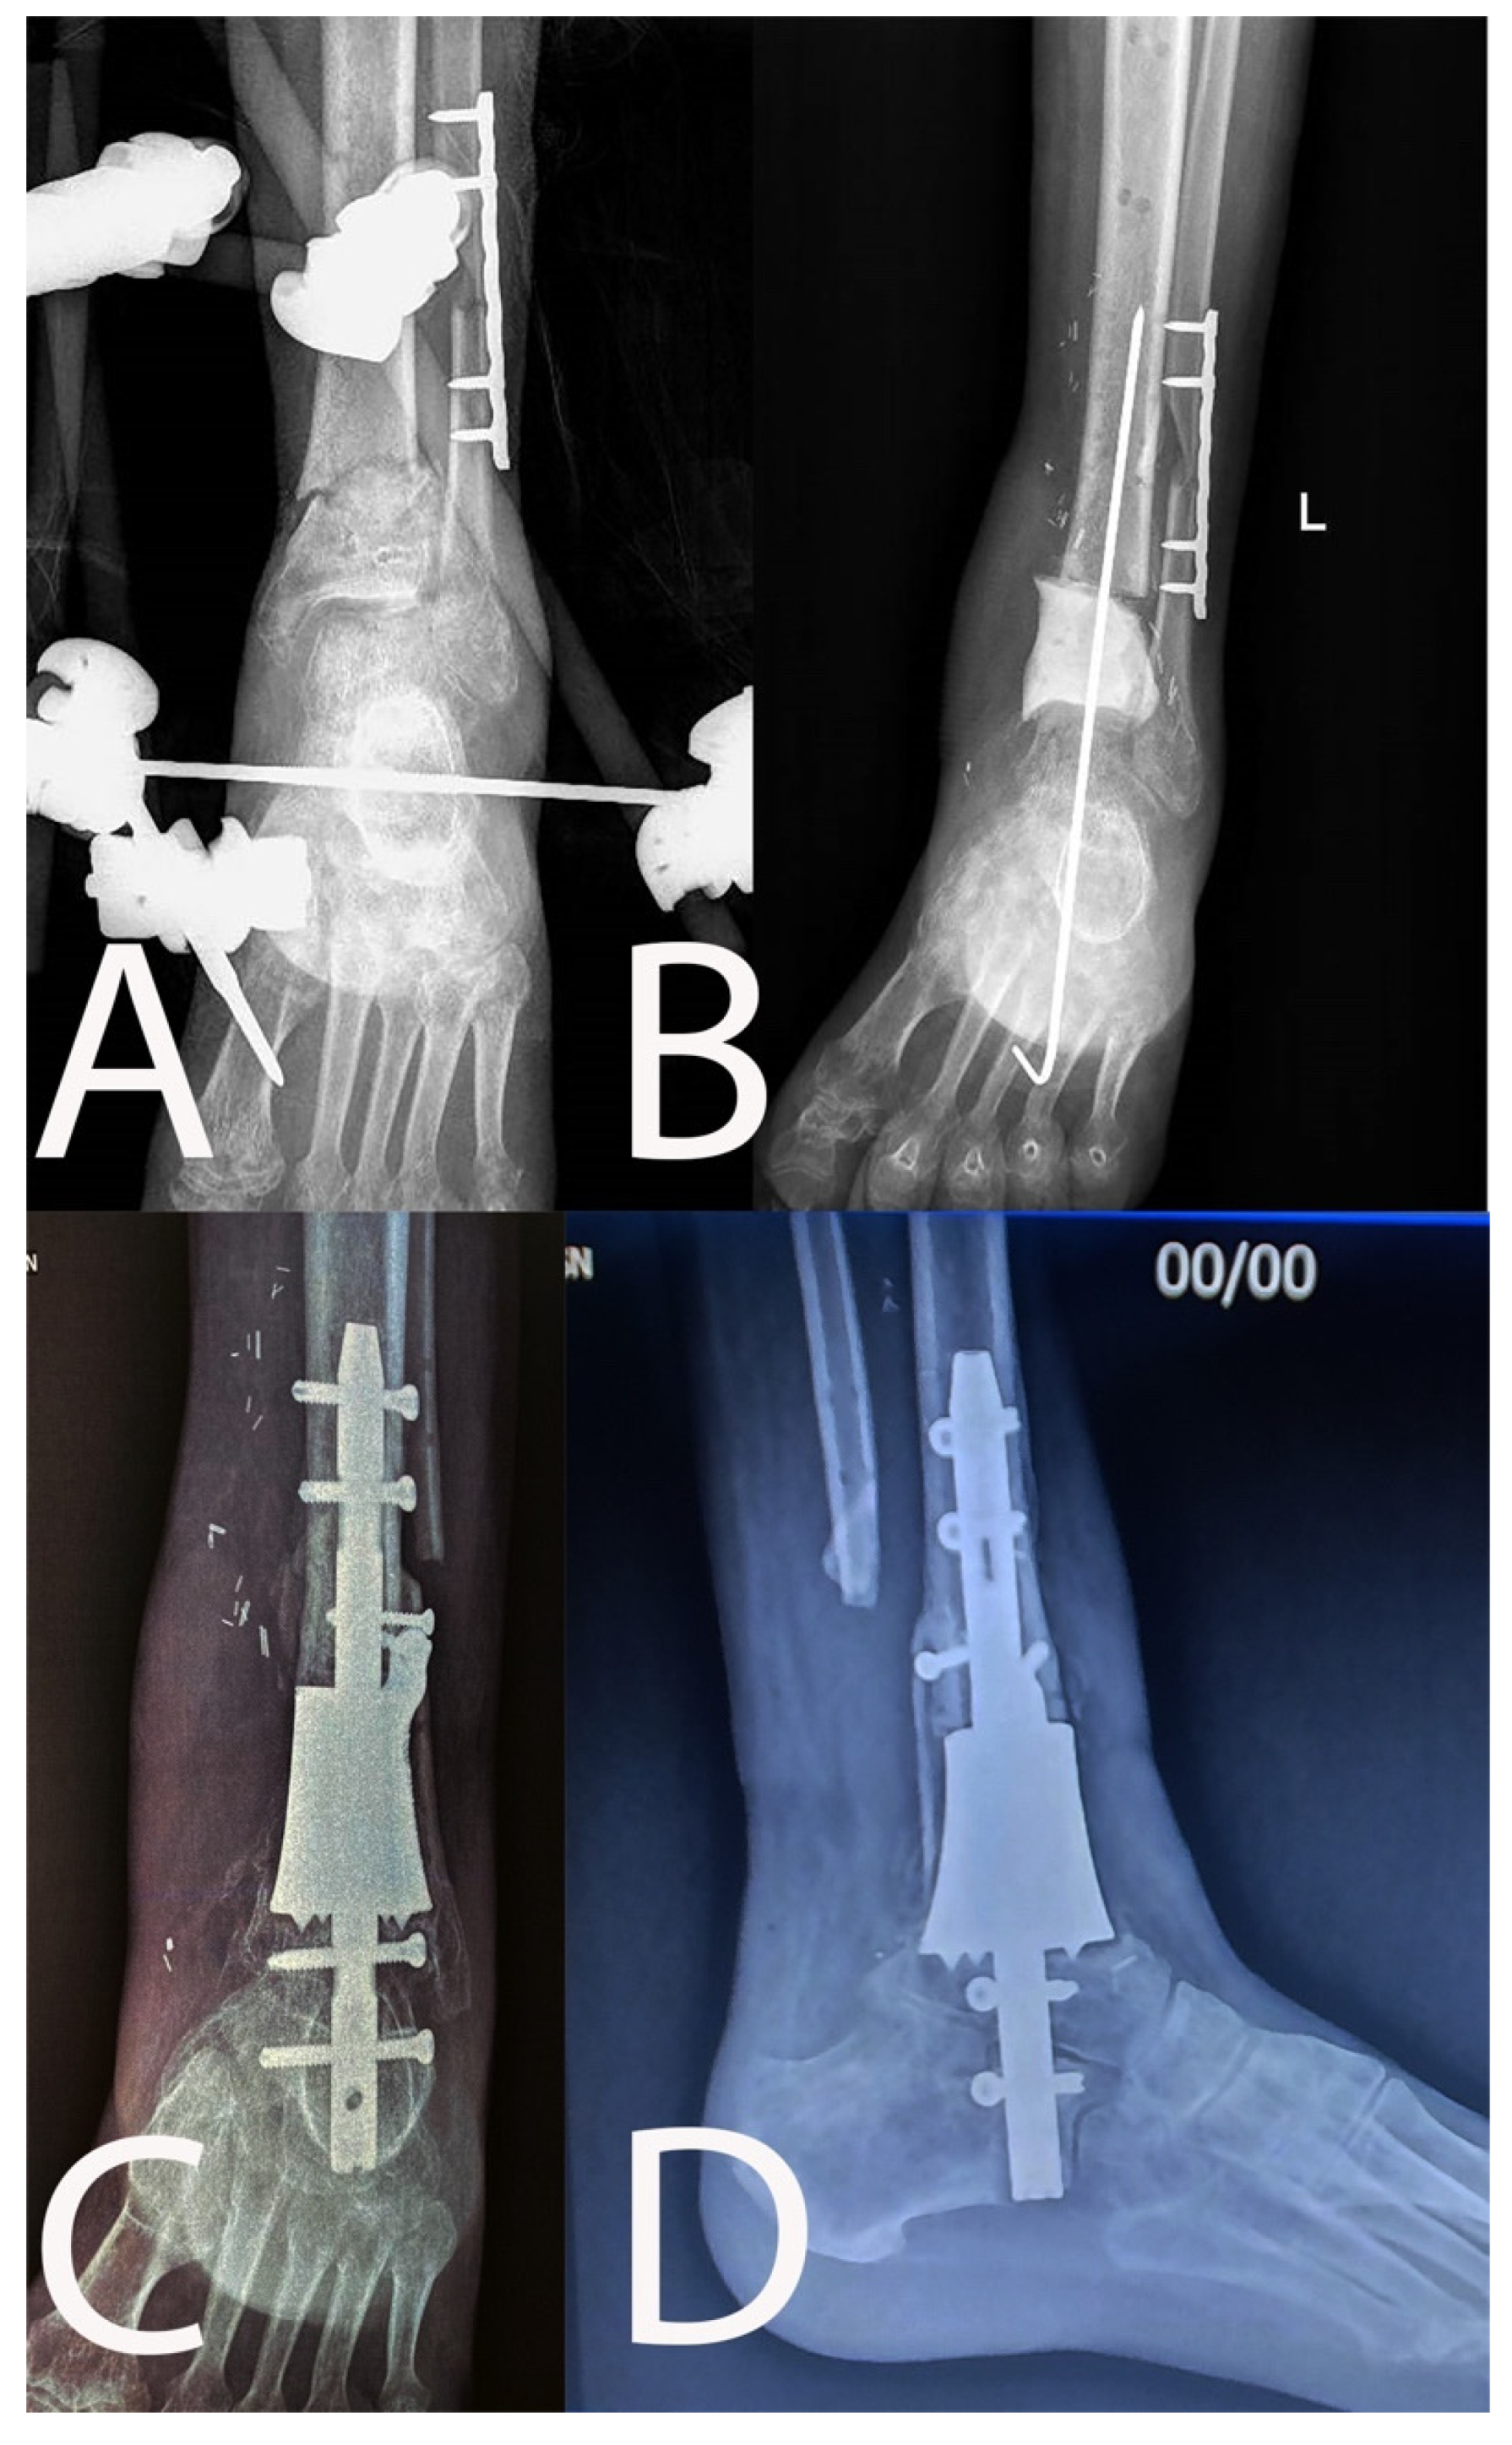

| 6 | 33, M | 1 | Yes | 3 | Yes | Type 4 | Type 4 A |

| 6 | Resection | No | 63 | MS CoNS | ALT | 16 | No | Persistence of infection, DVT | |

| 4 | 45, M | 2 | Yes | 2 | Yes | Type 4 | Type 4 A |

| 4 | Resection | Yes | 75 | E. coli | ALT | 33 | No | Hematoma | |